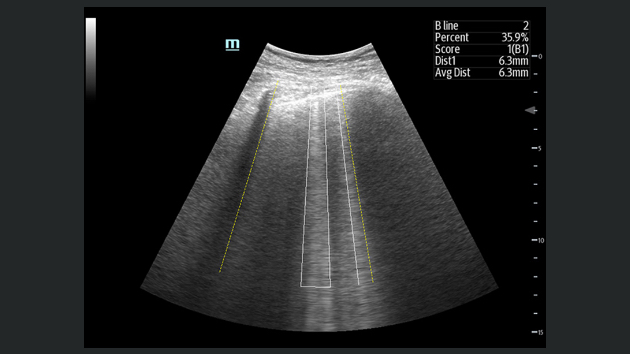

El sistema de ultrasonido TE9 estĂĄ dise?ado para ayudar a facilitar una mejor atenciĂłn al paciente y ampliar las capacidades de imagen para aplicaciones de anestesia, emergencias y cuidados crĂticos. Con funciones avanzadas, una gran pantalla tĂĄctil y una tecnologĂa de imagen superior, el TE9 es ideal para ayudar a mejorar la eficiencia clĂnica y la confianza en el diagnĂłstico. Las herramientas de automatizaciĂłn inteligentes brindan mediciones rĂĄpidas y reproducibles para exĂĄmenes y procedimientos fiables, incluso en entornos de gran presiĂłn.